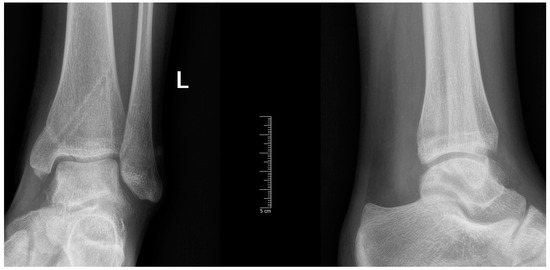

| Imaging: | X-ray | Arthroscopy | MRI | |||

|---|---|---|---|---|---|---|

| Classification | Berndt and Harty [21]—1959 | Guhl [22]—1982 | ICRS by Brittberg and Winalsky [23]—2003 | DiPaola [24]—1991 | Hefti [4]—1999 | Ellerman [15]—2019 |

| Stage 1 | Small subchondral compression | Intact Lesion | A stable lesion of the softened area covered by intact cartilage | Thickening of articular cartilage and low signal changes | Small change in signal, without clear fragment margins | Epiphyseal cartilage lesion with necrotic center |

| Stage 2 | Partially detached osteochondral fragment | A lesion with signs of early separation | Lesions with partial discontinuity which are stable when probed | Articular cartilage is breached, with a low signal rim behind the fragment indicating fibrous attachment | Osteochondral fragment with clear margins, without fluid in between | Epiphyseal cartilage lesion with complete or incomplete rim calcification |

| Stage 3 | Completely detached, non-displaced | Partially detached lesion | Lesions with complete discontinuity which are not dislocated (Dead in situ) | High signal changes behind the fragment indicate synovial fluid between the fragment and the underlying subchondral bone | Fluid is partially visible between the fragment and bone | Partially or completely ossified lesion |

| Stage 4 | Completely detached and displaced—loose body | Craters with loose bodies (salvageable or non-salvageable) | Empty defect bed with loose or dislocated fragment | Loose body | Fluid surrounds the fragment but it is still in situ | Healed osseous lesion with scar |

| Stage 5 | Scranton and McDermott modification: Subchondral Cyst | - | - | - | The fragment is completely detached and displaced | Unhealed, detached osseous lesion (Sequestrum) |